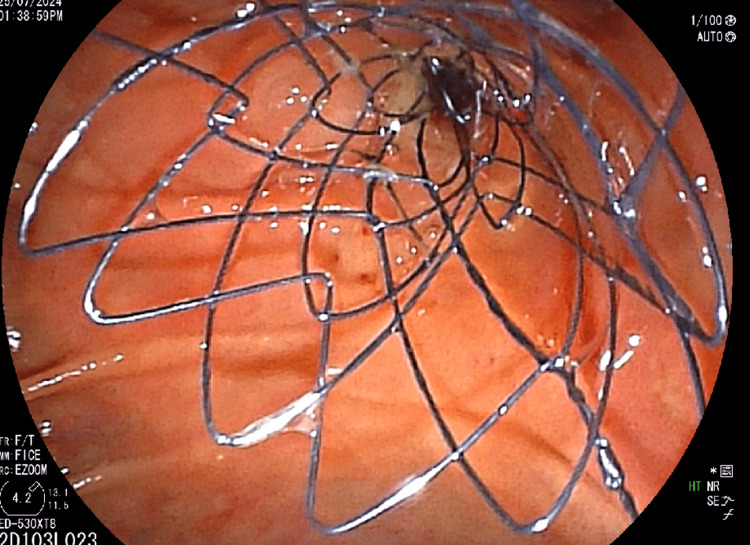

The patient underwent endoscopic retrograde cholangiopancreatography (ERCP), which showed significant stricture of the mid-CBD caused by the external mass, leading to the placement of a biliary stent (10 mm x 6 cm) post-biliary sphincterotomy to relieve obstructive jaundice (Figure 4). Palliative chemotherapy with a platinum-based compound and paclitaxel was initiated, accompanied by planned palliative radiotherapy to reduce the tumor burden and alleviate symptoms. Regular follow-ups with liver function tests and imaging studies were scheduled to monitor the response to treatment and adjust the therapy as needed.